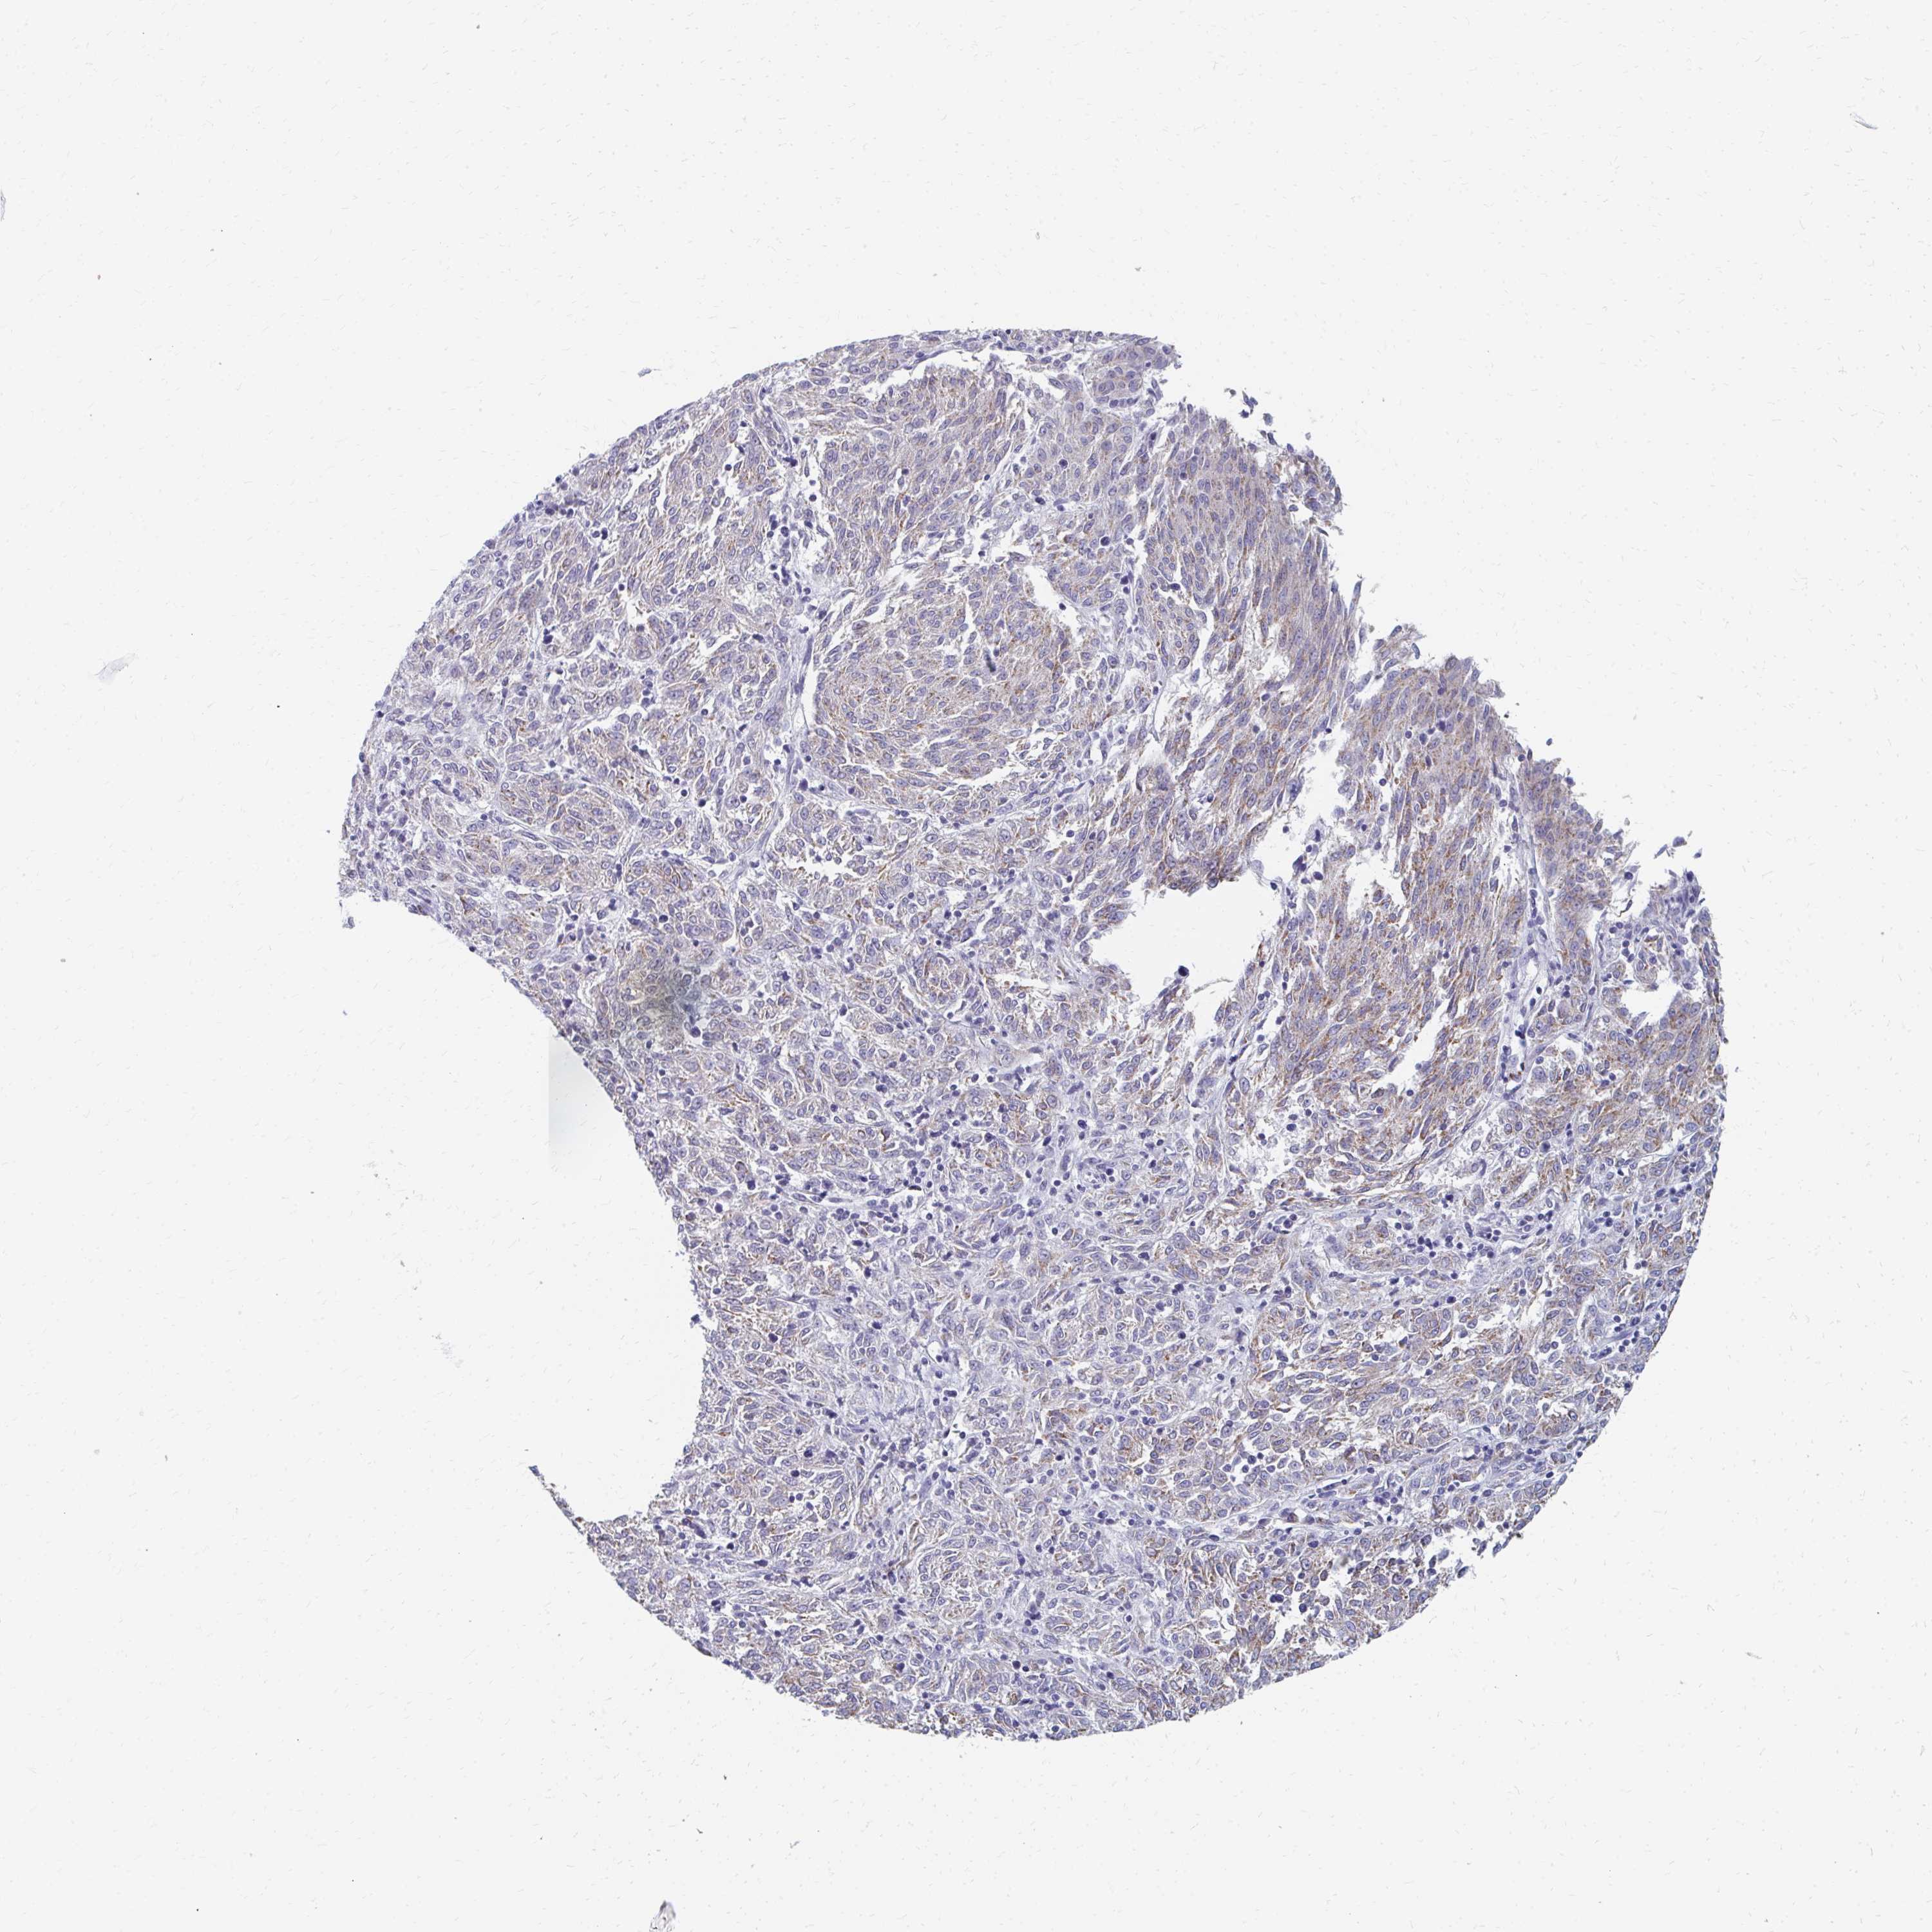

MELANOMA - Protein expressioni

A mouse-over function shows sample information and annotation data. Click on an image to view it in a full screen mode. Samples can be filtered based on level of antibody staining by selecting one or several of the following categories: high, medium, low and not detected. The assay and annotation is described here.

Note that samples used for immunohistochemistry by the Human Protein Atlas do not correspond to samples in the TCGA dataset.

Antibody stainingi

Antibody staining in the annotated cell types in the current human tissue is reported as not detected, low, medium, or high, based on conventional immunohistochemistry profiling in selected tissues. This score is based on the combination of the staining intensity and fraction of stained cells.

Each image is clickable and will lead to virtual microscopy that enables deeper exploration of all samples and also displays staining intensity scores, fraction scores and subcellular localization as well as patient and tissue information for each sample.

Antibody HPA060076

Staining

High

Medium

Low

Not detected

Intensity

Strong

Moderate

Weak

Negative

Quantity

>75%

75%-25%

<25%

None

Location

Nuclear

Cytoplasmic/membranous

Cytoplasmic/membranous,nuclear

Malignant melanoma, NOS

Malignant melanoma, Metastatic site